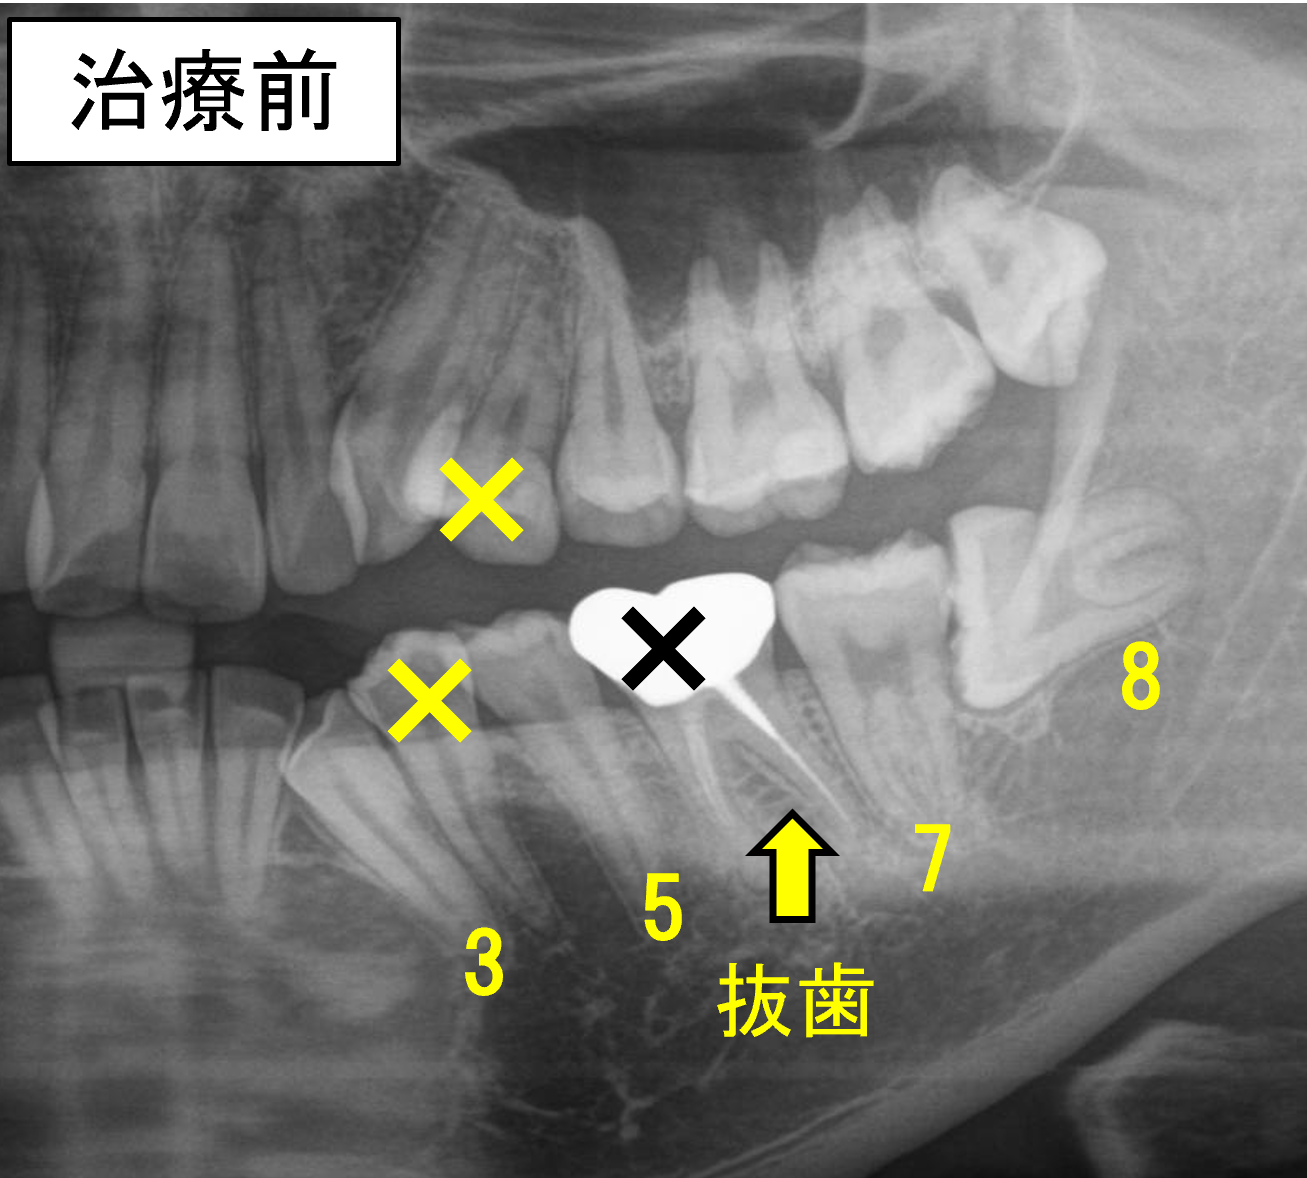

◆【症例7】パターン③ 状態の悪い7番(根管治療歯)を抜いて、親知らずを利用したケース

根管治療を行っていた状態の悪い7番を抜いて、親知らず(8番)を利用した症例をご紹介します。

通常であれば、8番を抜いて、普通に並べる症例だと思いますが、本人と相談の上、根管治療歯の7番を抜いて、健全な8番を利用することとしました。

25歳ですが、7番を抜くと8番が自然に生えてきます。多少傾斜して生えるため、矯正治療で起こしながら手前に動かしました。

左下7番は根管治療歯で余り状態も良くなかったため、左下7番を抜歯し、8番を利用しました。

- 抜歯部位:上顎左右8番、右下8番、左下7番